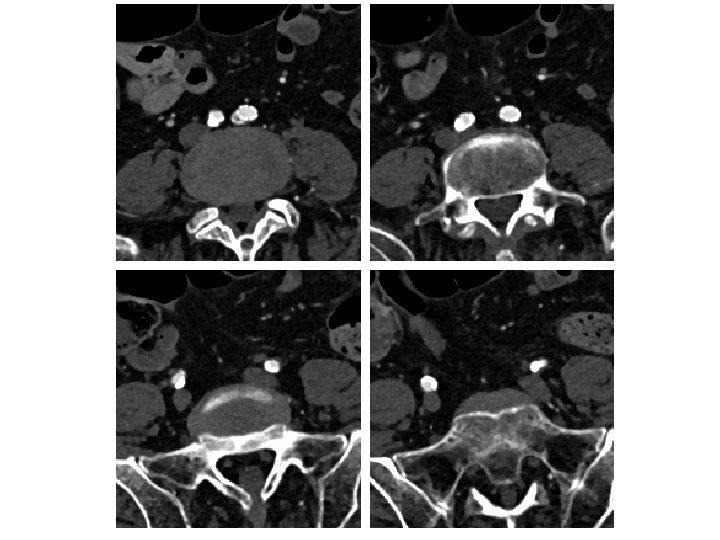

SE Stent Compression Is A Problem • 53 patients (28 females) prospective aorto-iliac stent • 165 aorto-iliac stents placed with CBCT confirmation • 20/53 patients underwent adjunctive procedures after the primary stenting • In 24. 5% (13/53) cases, adjunctive procedures were indicated solely on the CBCT findings • 26 of the 53 patients had kissing stents placed at the aortic bifurcation • Of the kissing stent patients, 34. 6% required adjunctive procedures and in two thirds these stent compressions were detected only by CBCT. Törnqvist P, et al. Utility of Intra-operative Cone Beam Computed Tomography in Endovascular Treatment of Aorto-iliac Occlusive Disease. Eur J Vasc Endovasc Surg. 2015

Kissing SE Stents Often Asymmetric Subgroup analysis between the types of stents used and adjunctive procedure showed that self expandable stents were more prone to need adjunctive procedure in the common iliac artery (p =. 048) Törnqvist P, et al. Utility of Intra-operative Cone Beam Computed Tomography in Endovascular Treatment of Aorto-iliac Occlusive Disease. Eur J Vasc Endovasc Surg. 2015